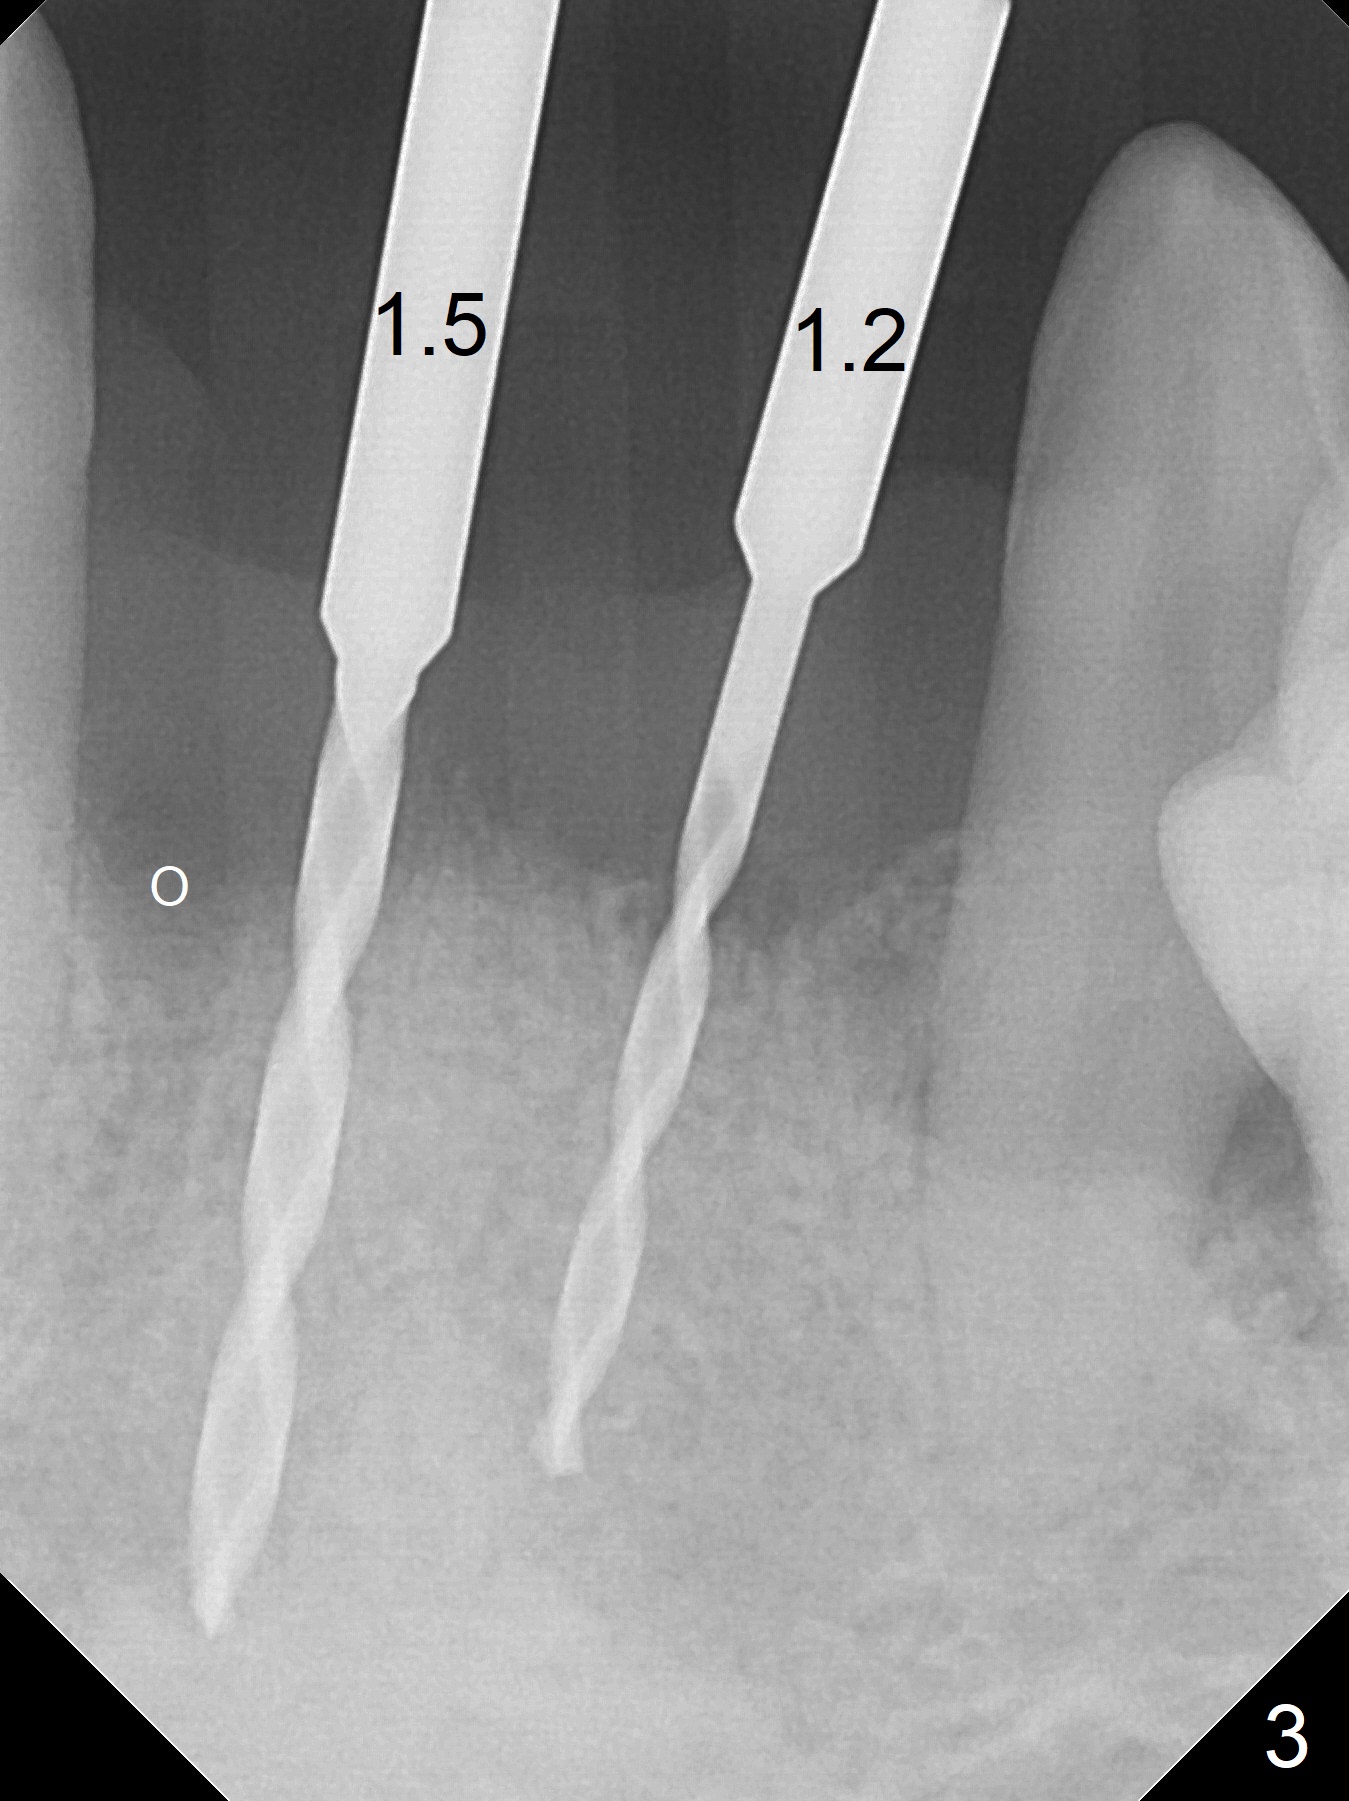

After extraction of 4 of the lower incisors, there are basically 2 sockets (#23/24 and 25/26), separated by the apparently midline bone (Fig.1 red line).  In spite of using Lindamann bur to move the 25/26 osteotomy mesially, a 3x14(2) mm dummy implant remains close to the tooth #27 (Fig.2).  The terminal branch of the Incisive Canal (<) is located between the lateral and central incisors.  A de novo osteotomy (Fig.3 (1.5 mm drill)) is made mesial to the original one (O).  While the 3x14(2) mm dummy implant is incompletely placed at #25/26, a 3x14(4) mm 1-piece one is placed at #23/24 (Fig.4).  Finally the same implant is placed at #25/26 with placement of mineralized cortical/cancellous bone (Fig.5 *).  When the large sockets are sutured, the supraerupted teeth #7-9 touch the lower gingiva (Fig.6).  The incisal edge is reduced for clearance (Fig.7).  Periodontal dressing is less likely to be dislodged with the incisal edge reduction (Fig.8,9).  A provisional FPD is fabricated 1 week postop.  Hard (Fig.10) and soft (Fig.11,12) tissues heal 5.5 months postop.  The patient returns for crown cementation 3 months post impression (9 months postop, Fig.13,14).